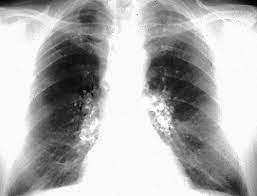

En las radiografías de tórax (CXR), estas máculas de carbón se presentan como pequeñas opacidades difusas, especialmente notables en las regiones pulmonares superiores. La distribución predominante de estas opacidades en los lóbulos superiores es característica de la neumoconiosis del trabajador del carbón y refleja la tendencia del polvo a acumularse en estas áreas debido a la dinámica de ventilación y la gravedad.

Sin embargo, a medida que la exposición al polvo de carbón continúa y la enfermedad progresa, puede desarrollarse la neumoconiosis complicada del trabajador del carbón, también conocida como fibrosis masiva progresiva (FMP). En esta etapa, se produce una conglomeración de las máculas de carbón y una significativa contracción y fibrosis en las zonas pulmonares afectadas, principalmente en los lóbulos superiores. La progresión de la enfermedad lleva a la formación de grandes áreas de fibrosis que se asemejan a las características radiográficas observadas en la silicosis complicada, otra forma grave de neumoconiosis en la que también se observa una fibrosis masiva y progresiva.

La neumoconiosis complicada del trabajador del carbón se manifiesta en las radiografías de tórax por la presencia de grandes opacidades conglomeradas y una fibrosis más pronunciada. Esta progresión puede resultar en una notable disminución de la función pulmonar, síntomas clínicos como disnea y tos crónica, y una reducción en la calidad de vida del paciente.

En términos radiográficos, un hallazgo distintivo de la silicosis es la calcificación de la periferia de los ganglios linfáticos hilares, conocida como calcificación de «cáscara de huevo». Este patrón radiográfico es un marcador característico que sugiere fuertemente la presencia de silicosis, aunque no es observado en todas las presentaciones de la enfermedad. La calcificación de la cáscara de huevo se refiere a la calcificación de los bordes de los ganglios linfáticos hilares y mediastínicos, que se observa en las imágenes radiográficas y es indicativa de una respuesta inflamatoria crónica prolongada.

En las radiografías de tórax, la asbestosis se manifiesta con características radiográficas distintivas. Estas incluyen la presencia de rayas lineales en las bases pulmonares, que reflejan la fibrosis subpleural y el engrosamiento de las estructuras pulmonares. Las imágenes también pueden mostrar opacidades de diversas formas y tamaños, que corresponden a los nódulos fibrosos en el pulmón. En casos avanzados de asbestosis, pueden observarse cambios en el patrón de panal de abeja, que es una representación radiográfica de fibrosis avanzada y destrucción de las estructuras pulmonares.